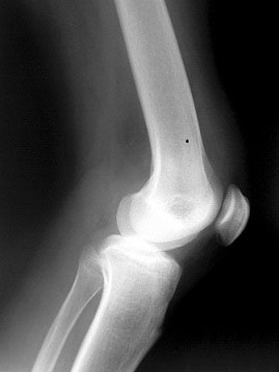

2. The other main category of knee pain is lateral or medial knee pains (on the inside or outside of your leg). These are more tricky and have a multitude of potential causes. Overwhelmingly, the direct cause of the knee pain is that the knee is trying to track in a different plane of motion to the arm of the crank. The knee is a simple hinge joint which is only reliably able to function if it is moving in the correct plane of movement. Any deviation of the knee in terms of torsional movement (twisting) or ovality in the tracking of the knee will result in excessive loading of the lateral structures (the Iliotibial Band or “ITB” is a common culprit) or, less commonly, the medial structures of the knee. Often pain will feel dull and “behind the kneecap” – this is a sure sign that the patella, the large bone in the front of your knee which acts as a force couple for the quadriceps musculature, is being pulled forcibly out of its natural vertical plane of motion on the front of the femur.

Long-term abuse of the patella tracking will result in the thin lining of cartilage on the back face being worn down steadily until osteo-arthritis (bone on bone) is the end result. Patellar mal-tracking is the most common of the knee pains that we see and can be caused by many different issues – almost all of which are either above or below the knee itself. Tight external rotators in the hip, tight and overactive hip flexors, weak medial quadriceps, a collapsing arch, improper cleat placement, too high or low a seat, or incorrect foot correction (rearfoot AND forefoot) can all play a part in forcing the knee to track in the wrong plane of motion.